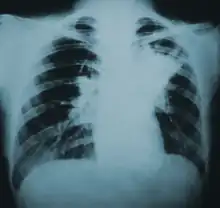

| Lung infiltration in blastomycosis. | |